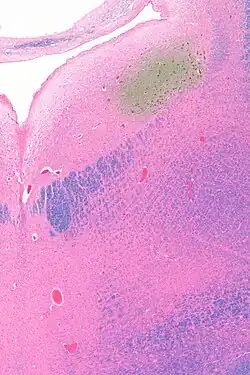

Anatomy

The locus coeruleus (LC) is located in the posterior area of the rostral pons in the lateral floor of the fourth ventricle. It is composed of mostly medium-size neurons. Melanin granules inside the neurons contribute to its blue colour. Thus, it is also known as the blue nucleus, or the nucleus pigmentosus pontis (heavily pigmented pontine nucleus).[5] The neuromelanin is formed by the polymerization of norepinephrine and is analogous to the black dopamine-based neuromelanin in the substantia nigra.

The locus coeruleus is affected in many forms of neurodegenerative diseases: genetic and idiopathic Parkinson's disease, progressive supranuclear palsy, Pick's disease, and Alzheimer's disease. It is also affected in Down syndrome.[29] For example, there is up to 80% loss of locus coeruleus neurons in Alzheimer's disease,[30] Mouse models of Alzheimer's disease show accelerated progression after chemical destruction of the locus coeruleus.[31] Neurofibrillary tangles, a primary biomarker of Alzheimer's disease, may be found in the locus coeruleus decades before any clinical symptoms.[32] The norepinephrine from locus coeruleus cells in addition to its neurotransmitter role locally diffuses from "varicosities". As such it provides an endogenous anti-inflammatory agent in the microenvironment around the neurons, glial cells, and blood vessels in the neocortex and hippocampus.[18] It has been shown that norepinephrine stimulates mouse microglia to suppress Aβ-induced production of cytokines and promotes phagocytosis of Aβ.[18] This suggests that degeneration of the locus coeruleus might be responsible for increased Aβ deposition in AD brains.[18] Degeneration of pigmented neurons in this region in Alzheimer's and Parkinson's disease can be visualized in vivo with Neuromelanin MRI.[33] Since the marked degeneration of locus coeruleus, and the neuroprotective properties of noradrenaline, Ian Robertson proposed the "Noradrenergic Theory of Cognitive Reserve" [34] which postulates that the upregulation of the locus coeruleus-noradrenergic system throughout the lifespan may enhance cognitive stimulation contributing to cognitive reserve preventing from neurodegeneration. Evidence appear to support this theory reporting the locus coeruleus integrity primarily responsible of biological brain maintenance,[35][36][37] including brain clearance,[38] cognitive efficiency, and reduced neuropathological burden.[35][39][40][41]